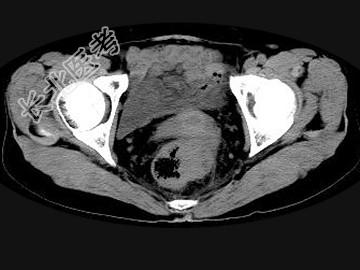

- 单项选择题男,56岁, 排便形状改变,便后不尽感, CT检查如图所示,下列说法正确的是 ( )

A、肠壁上有蒂状新生物

B、其表面光滑,边界清楚

C、肠腔未见狭窄

D、此为直肠息肉

E、此为直肠癌